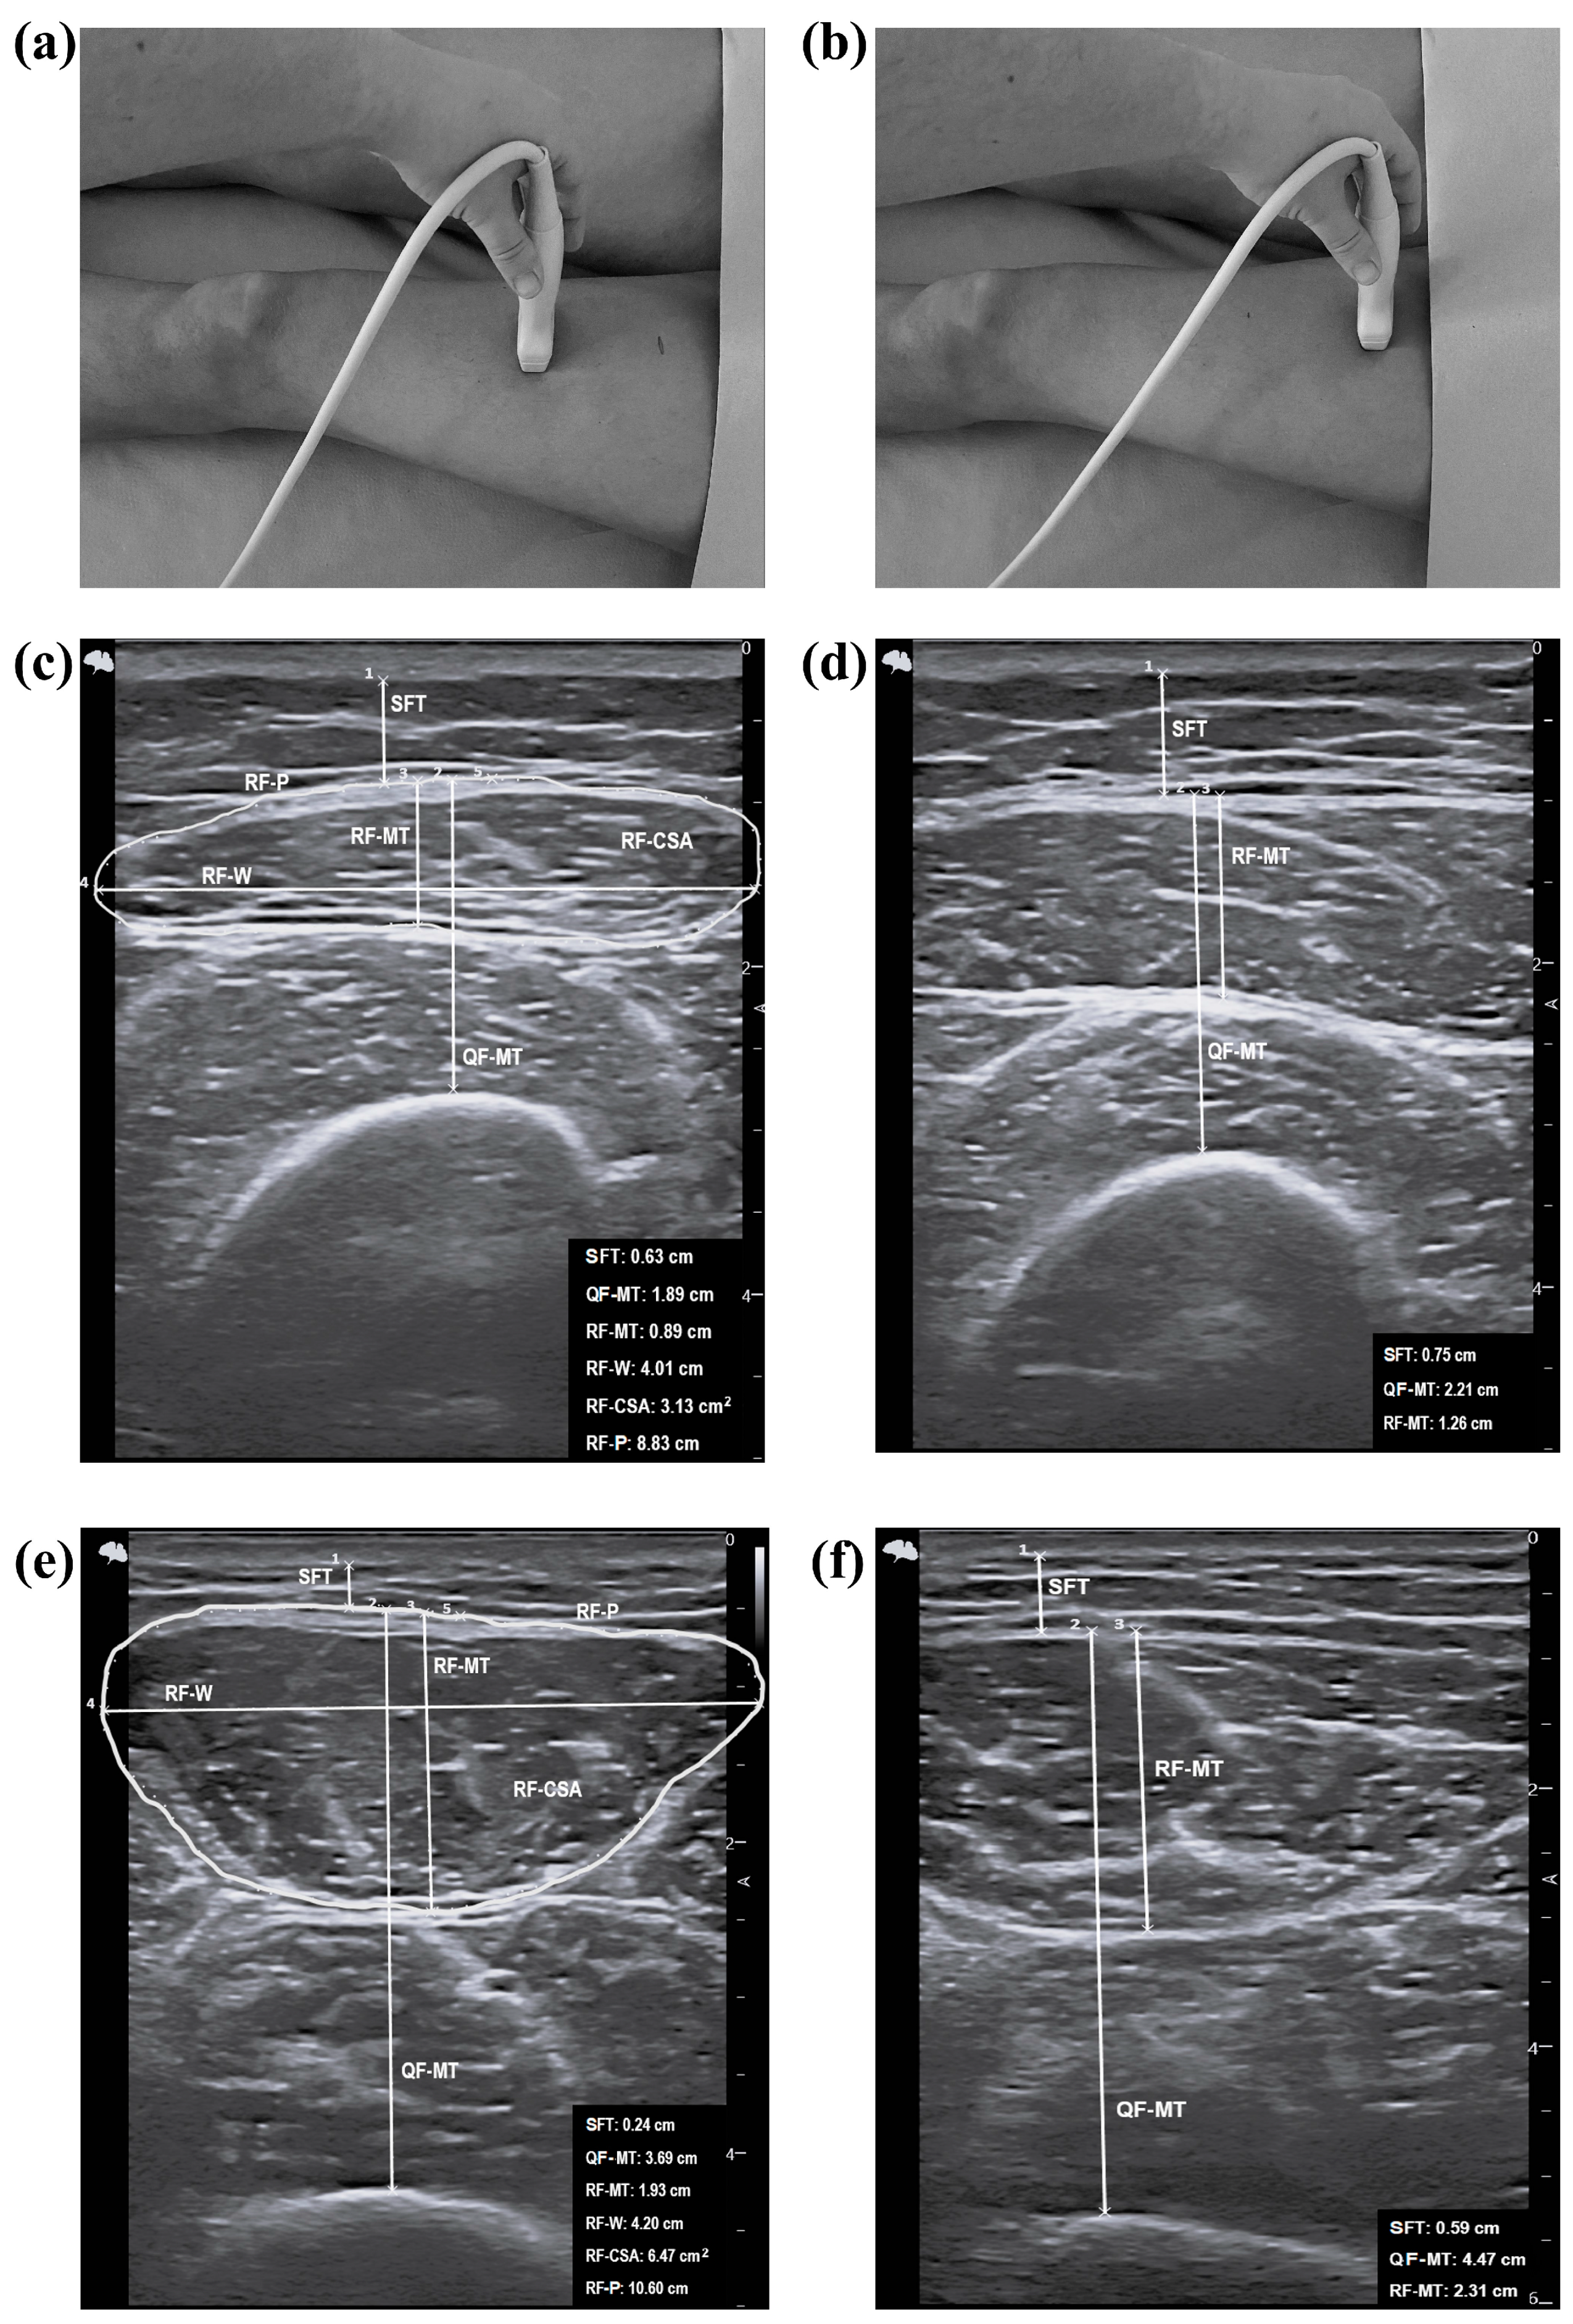

2.5. Assessment of Ultrasound Parameters

- Perkisas, S.; Baudry, S.; Bauer, J.; Beckwée, D.; De Cock, A.M.; Hobbelen, H.; Jager-Wittenaar, H.; Kasiukiewicz, A.; Landi, F.; Marco, E.; et al. Application of Ultrasound for Muscle Assessment in Sarcopenia: Towards Standardized Measurements. Eur. Geriatr. Med. 2018, 9, 739–757. [Google Scholar] [CrossRef]

| Upper leg at 30% | ||||||

| SFT (cm) | All | 1.28 ± 0.57 | 0.80 ± 0.39 | 0.004 | <0.001 | 0.221 |

| Men | 0.75 ± 0.58 | 0.54 ± 0.18 | 0.654 | |||

| Women | 1.41 ± 0.50 | 1.16 ± 0.29 | 0.203 | |||

| QF-MT (cm) | All | 2.31 (0.89) | 2.81 (1.35) | 0.058 | <0.001 | 0.316 |

| Men | 2.97 (0.30) | 3.20 (1.20) | 0.565 | |||

| Women | 2.14 (0.74) | 2.20 (0.38) | 0.572 | |||

| RF-MT (cm) | All | 1.32 (0.45) | 1.33 (0.82) | 0.205 | <0.001 | 0.377 |

| Men | 1.79 (0.75) | 1.90 (0.75) | 0.848 | |||

| Women | 1.15 (0.43) | 1.10 (0.24) | 0.621 | |||

| RF-W (cm) | All | 3.89 ± 0.38 | 4.05 ± 0.22 | 0.109 | <0.001 | 0.345 |

| Men | 4.37 ± 0.22 | 4.15 ± 0.17 | 0.064 | |||

| Women | 3.77 ± 0.32 | 3.91 ± 0.22 | 0.346 | |||

| RF-CSA (cm2) | All | 4.06 (1.60) | 4.67 (3.10) | 0.085 | <0.001 | 0.333 |

| Men | 7.02 (3.47) | 6.61 (2.33) | 0.749 | |||

| Women | 3.62 (1.38) | 3.90 (0.91) | 0.850 | |||

| RF-P (cm) | All | 8.97 (0.92) | 9.75 (1.69) | 0.014 | <0.001 | 0.261 |

| Men | 11.12 (1.91) | 10.60 (0.85) | 0.655 | |||

| Women | 8.82 (0.73) | 9.28 (0.76) | 0.120 | |||

| Upper leg at 50% | ||||||

| SFT (cm) | All | 1.45 ± 0.59 | 1.08 ± 0.47 | 0.061 | <0.001 | 0.319 |

| Men | 0.92 ± 0.71 | 0.76 ± 0.17 | 0.337 | |||

| Women | 1.57 ± 0.49 | 1.52 ± 0.36 | 0.981 | |||

| QF-MT (cm) | All | 3.29 ± 0.71 | 3.80 ± 1.14 | 0.264 | <0.001 | 0.392 |

| Men | 4.04 ± 0.71 | 4.49 ± 0.97 | 0.406 | |||

| Women | 3.12 ± 0.59 | 2.82 ± 0.37 | 0.220 | |||

| RF-MT (cm) | All | 1.64 (0.33) | 1.93 (0.95) | 0.114 | <0.001 | 0.347 |

| Men | 2.25 (0.89) | 2.32 (0.55) | 0.848 | |||

| Women | 1.62 (0.28) | 1.53 (0.47) | 0.423 | |||